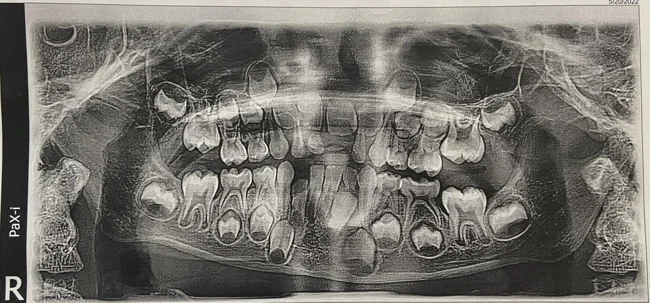

19. «Рентгеновский снимок зубов моего шестилетнего ребёнка»